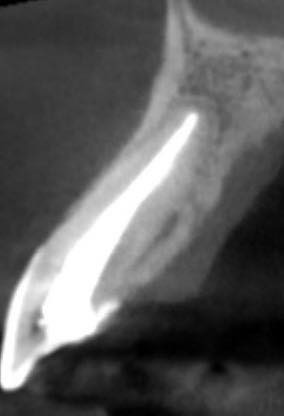

Treatment of the palato-radicular groove and cemental tear: a case report

Deep probing depth and CT scan can be done to diagnose the periodontal disease and cemental tears. Open flap surgery to remove tears of cementum and composite resin fills the groove. Then, GTR with FDBA and collagen membrane.

右上側門牙經由牙周再生手術,誘導牙周細胞的再生,修復先前受損的牙周組織。

GTR: Tetracycline + NS, Gentamicin irrigation, BioOss(s) + Lyoplant